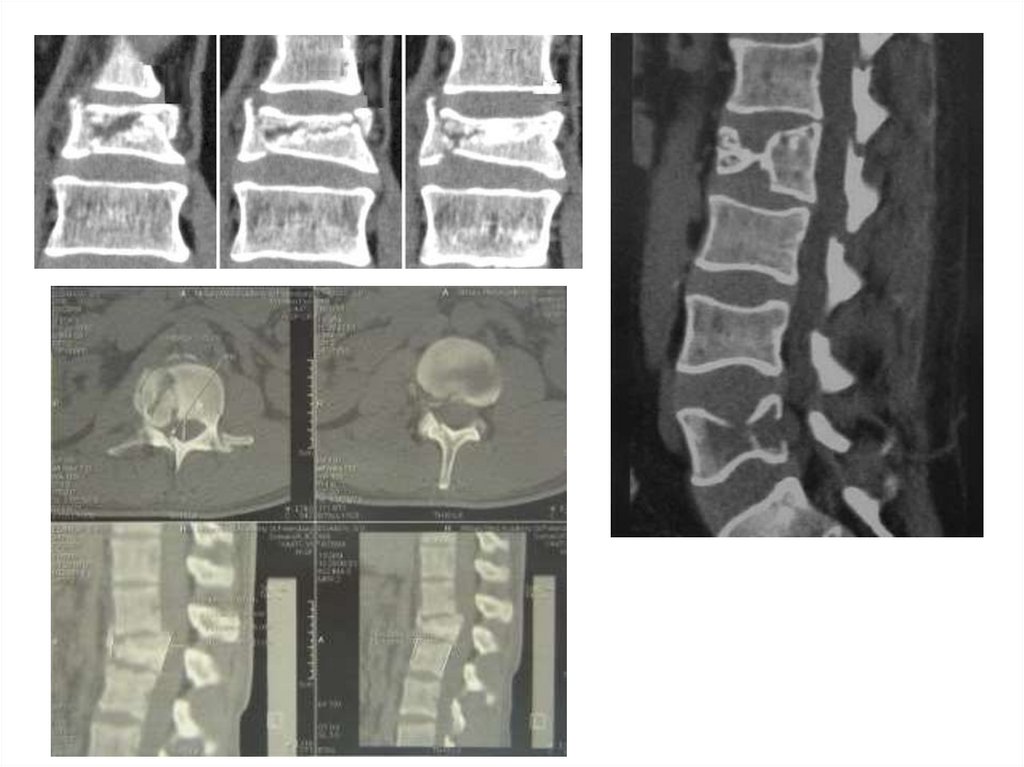

КТ и МРТ при переломе позвонков

• Состояние спинного мозга

МРТ при переломах

позвонков